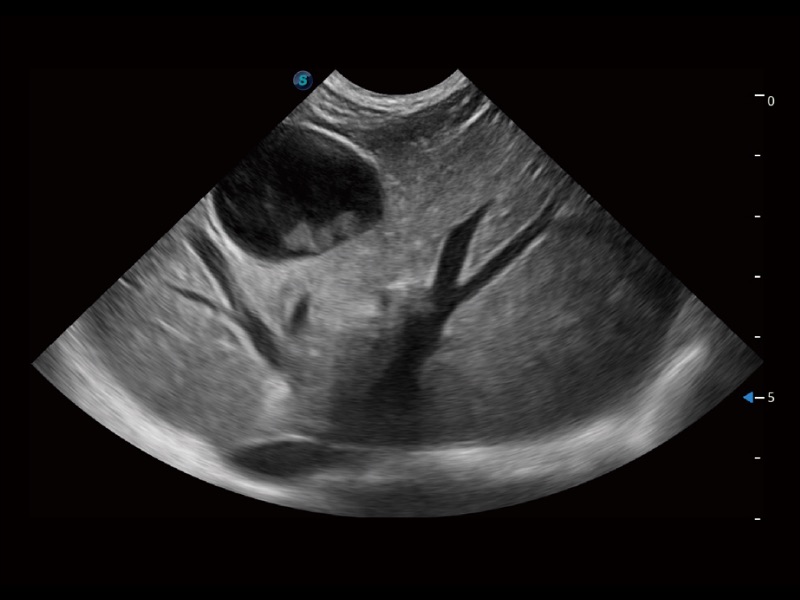

动物是人类最亲密的朋友和最值得信赖的伙伴。乐玩lewin国际也一直致力于探索动物专用的超声影像解决方案。全新推出的ProPet系列,是乐玩lewin国际在动物超声影像智能化、专业化、精准化的一次跨越式革新。动物不能用言语来表述自己的不适,通过超声影像,ProPet系列搭建了动物医生与不同物种沟通的“桥梁”,为动物医生注入了“治愈之力”。 ProPet 70将是您值得信赖的超声伙伴。它配备了复合材料线阵探头,帮助动物医生获得卓越精准的临床图像。同时ProPet 70直观便捷的操作体验以及专业的测量工具,可为不同体型和生理结构的动物带来全面临床评估,切实为动物医生提供智能、专业、精准的超声影像解决方案。

ProPet 70 进一步提升了微米成像算法,更加注重对基础原始图像的还原和保留,在有效减少斑点噪声、增强组织边界显示的同时,避免过度优化丟失真实的解剖信息。

ProPet 70专为动物医生设计,对不同的动物体型和生理结构作出了针对性的优化。通过动物影像专用软件,可满足个性化的应用需求,帮助动物医生获得更精确的诊断数据。

ProPet 70 全新的动物超声智能软件和丰富的探头群,为动物医生提供了高清晰度和精细分辨率的图像,无论在宠物、马科、畜牧还是实验室动物等应用中都可以轻松应对,为您的日常工作带来满意的体验。